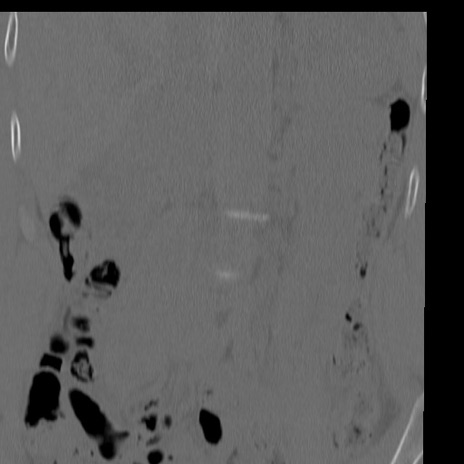

症例3 腰椎CT(冠状断像)

腰椎CT